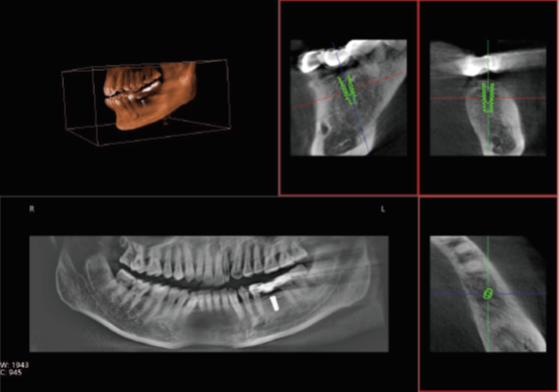

口腔CT是口腔科專用的CT(Cone Beam Computed Tomography), 也就是CBCT,即錐形束CT,采用錐束形X線掃描,可以顯著提高X線利用率,只需圍繞投照體做環形數字式投照即可獲取重建所需的全部原始數據,在計算機中重組,進而獲得三維圖像。通過數據采集方式的改進,口腔CT不僅提高了醫學影像的掃描分辨率,也將放射劑量降低到了一個新的水平。那么,哪些口腔治療會使用到口腔CT呢?

眾所周知,在口腔內種植牙齒是十分精細的手術,沒有先進的可視化影像設備支持的種植牙手術,就猶如盲人摸象,手術效果難以預知??谇籆T影像能測量牙槽骨的高度和寬度,估計種植部位,與下頜阻生磨牙相關的低位下牙槽神經管影響頜骨的疾病的病理學評估。

正常情況下,牙齒的排列不在一個平面上, 且具有一定的生理弧度,普通X線往往使圖像相互重疊,使圖片看不清楚。但是,口腔CT的三維成像對牙體、牙根、牙周膜等微細結構顯示更加清晰??梢詭椭t生了解斷根,牙根內吸收、根管鈣化、牙根結石、牙槽骨退縮等情況,能用于根管治療前尋找根管,術后評估根管充填情況,評估牙周炎程度及預期治療效果等。

正畸治療前的診斷分析是治療成功的重要步驟,口腔CT不僅能提供頭顱側位和曲斷片的信息,還可以評價每個牙齒的排列位置,牙根傾斜度,牙槽骨垂直向、頰舌向的骨量,骨密度等。用于牙列不齊矯正、牙頜面畸形矯正、牙周病輔助正畸。

口腔CT與全身CT相比,具有分辨率高、X射線輻射小、投照時間短、費用低、應用廣泛方便、操作簡單、可以配合第三方軟件獲得更多信息等優點。普愛醫療口腔CT使用脈沖透視采集圖像,在保證成像質量的基礎上,可有效降低患者吸收的輻射劑量。實現數字化三維容積重建,冠狀面、矢狀面、橫斷面的類CT成像效果,重建全景影像,選配牙種植系統,滿足牙周、牙根管、口腔矯形矯正、牙種植等臨床病例提供診斷依據。